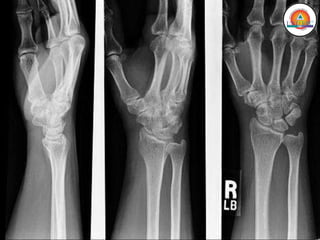

Huesos Cortos

• Forma cuboidal

• Se encuentran en la

muñeca (carpo) y tobillo

(tarso)

• Dan sostén y soportan

MIEMBRO SUPERIOR

• Antebrazo (Radio y Cúbito)

• Muñeca

• Mano (Carpo, Metacarpo y Falanges)

Huesos:

• Radio

• Cúbito

• Carpo

• Metacarpo

• Falanges

Huesos Cortos • Formacuboidal • Se encuentran en la muñeca (carpo) y tobillo (tarso) • Dan sostén y soportan peso